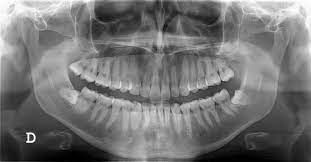

Presence of Caries that may involve or threaten to involve the Pulp Number, course, shape and length of root canals Calcification or obliteration of pulp cavity Internal and External Resorption Thickening of Periodontal Ligament Nature and extend of Periapical and Alveolar Bone Destruction